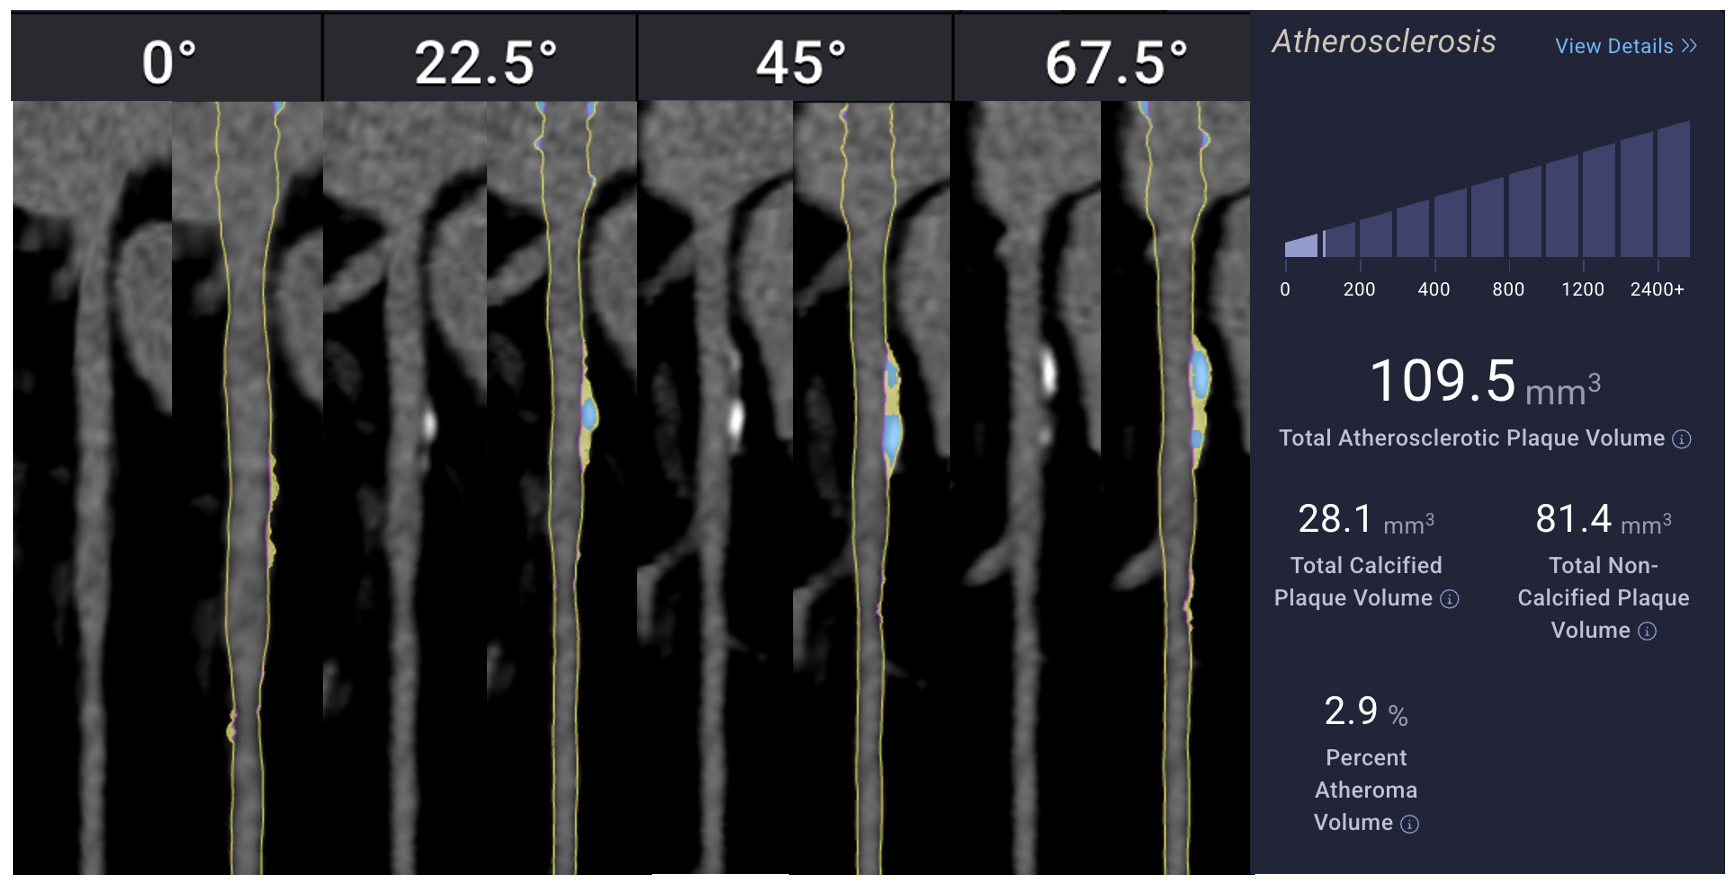

Artificial Intelligence Based CCTA to Assess Sex-Based Differences in Coronary Atherosclerosis with Low Clinical Atheroma Volume

Traditional calcium-based risk assessment tools may underestimate coronary artery disease (CAD) burden, particularly in females, due to their inability to capture non-calcified, high-risk plaque. Artificial intelligence (AI)-enhanced coronary computed tomography angiography (CCTA) offers more precise plaque characterization. This study evaluates sex-based differences in coronary plaque composition among individuals with low total atheroma volume (TAV <250 mm^3).

We conducted a retrospective cross-sectional analysis of 100 patients undergoing AI-based CCTA. Volumetric plaque metrics—including total, calcified (CAV), non-calcified (NCAV), and low-density non-calcified (LD-NCAV) atheroma volumes—were quantified by artificial intelligence augmented CCTA (Cleerly). Gender differences were evaluated using Welch’s t-tests and multivariable linear regression adjusted for age.

In unadjusted comparisons, women had significantly lower total plaque volume (p = 0.018) and non-calcified plaque volume (p < 0.001) compared to men. There were no significant differences in calcified (p = 0.52) or low-density non-calcified plaque (p = 0.16). Regression analysis confirmed that male gender was independently associated with greater total plaque (β = 37.4 mm^3, p = 0.003) and non-calcified plaque (β = 39.3 mm^3, p < 0.001). Age was a significant predictor of total, calcified, and non-calcified plaque burden, but not of low-density plaque. Model explanatory power was modest (R^2 ≈ 0.20).

Contrary to prior literature, men in this low-risk cohort had higher total and non-calcified plaque volumes than women, despite similar calcified burden. These findings highlight the limitations of calcification-based metrics in early risk stratification and underscore the utility of AI-based CCTA for detecting subclinical, non-calcified atherosclerosis. Future studies should explore reasons for these gender-based differences between studies and whether they influence long-term cardiovascular outcomes.